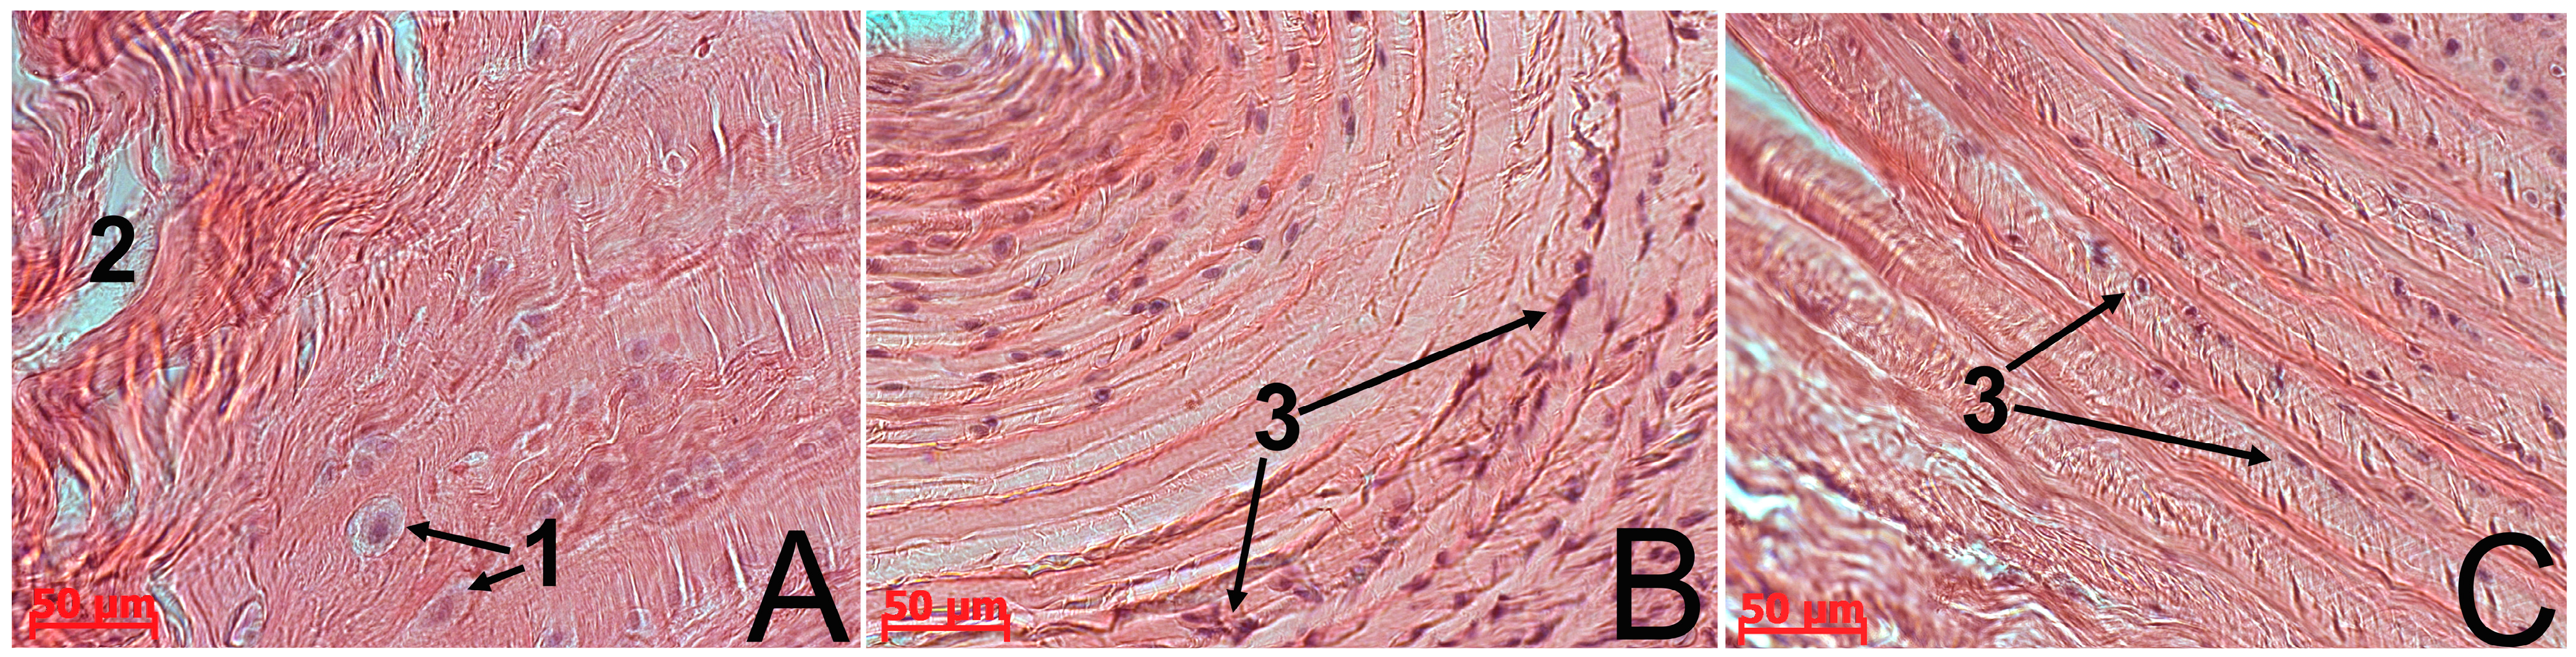

The results of the morphological study showed that restoration in the control and experimental group N1 was delayed, with insufficient synthesis of regenerative products. This was probably due to the failure of the body’s internal resources and the inability of the AF tissue to attain full recovery. Despite the cessation of compression in these groups, little spontaneous normalization, if at all, of all the test parameters occurred. At all the observation stages there was significant histological evidence of the degenerative damage of the AF tissue (Figure 2B): collagen fiber fragmentation, central tears and clefts, areas with low fibrochondrocyte density or a complete absence of cells, indistinct and interrupted AF/NP boundaries. AF cells either located singly or formed isogenic groups and their structure was heterogeneous (Figure 3A). Along with fibrocartilage-specific cells with ovoid nuclei, there were large chondrocyte-like cells with spherical nuclei surrounded by a wide rim of cytoplasm, which were located close to clefts. This fibrochondrocyte transformation with a strongly pronounced decline in cell density indicates the tension of regenerative processes in this area of AF [1]. At the same time, it should be noted that the method of the local MSC administration on the collagen sponge did not have a negative impact on the IVD structure.

Figure 3. The IVD Co6–Co7 in rats. In the control group of animals (A), large chondrocyte-like cells with spherical nuclei surrounded by a wide rim of cytoplasm (1) were detected near the clefts (2). In the case of native MSC administration (B) as well as the cryopreserved one (C), the AF cell population was represented by small fibrochondrocyte-like cells with ovoid nuclei (3).

Cryopreserved MSCs also stimulated the AF tissue regeneration in the IVD Co6–Co7, but the proliferative response of fibrochondrocytes was less pronounced compared to the native analogue. There was a tendency for improvement in the AF histological structure of the IVD Co6–Co7 on the 30th day (Figure 2D), namely with a decrease in collagen fiber fragmentation, a significant reduction in the area occupied by tears, clefts, and acellular sites, and an improvement of the AF/NP boundary contours. The population of AF cells, as well as in the case of native MSC administration, was represented by small fibrobrochondrocyte-like cells with ovoid nuclei, but cells were located mainly along collagen fibers, only penetrating their mass in some areas (Figure 3B,C).